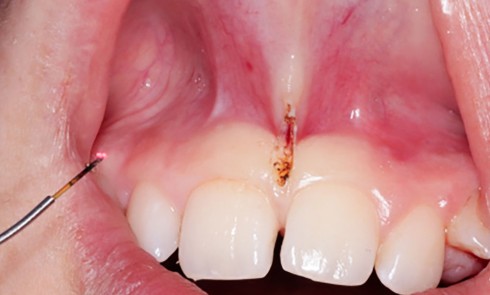

Article réservé à nos abonnés Frénectomie labiale au laser diode chez l’adolescent

Dans notre pratique orthodontique, le frein interincisif peut représenter une anomalie anatomique de la gencive et/ou de la muqueuse alvéolaire....